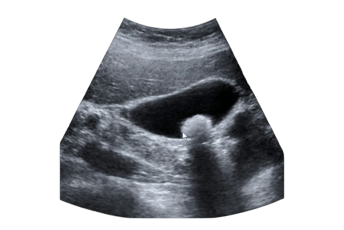

O diagnóstico costuma ser realizado por meio de ultrassonografia abdominal, um exame simples, indolor e altamente eficaz para detectar cálculos na vesícula. Em casos mais complexos, exames como tomografia ou ressonância magnética podem ser necessários.

O Ultrassom de abdome é o exame mais realizado para diagnósticar cálculos na vesícula biliar